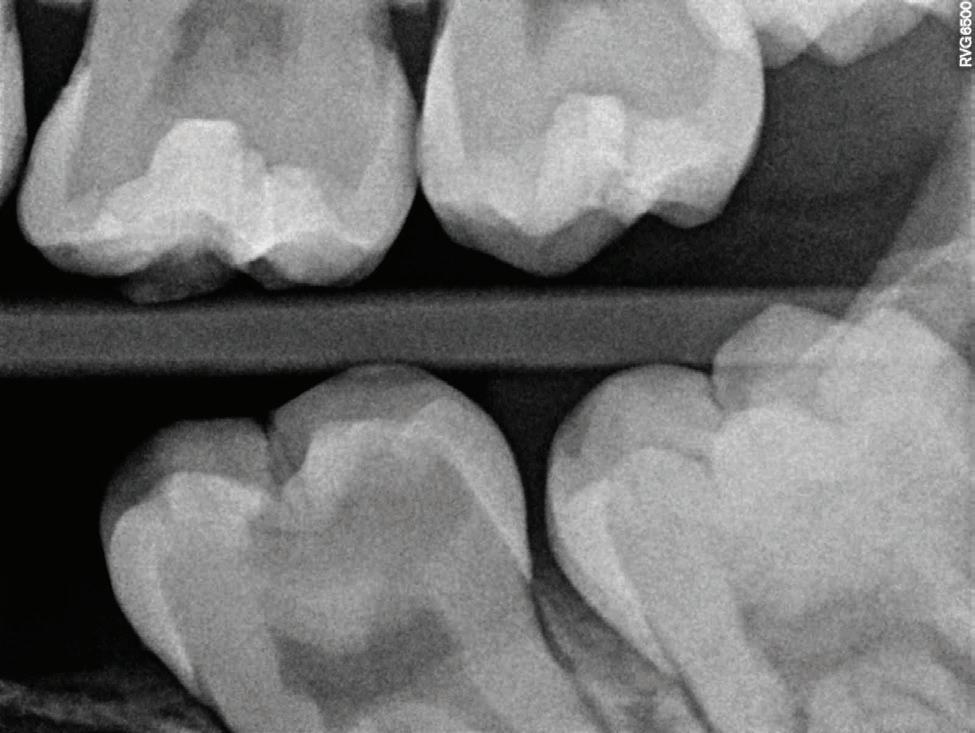

Clear radiographs are essential to accurate diagnosis and are a special test that dentists per form regularly many times throughout the day. Following the ALARA principle, we want to ensure we take a minimal number of radio graphs to ensure low radiation dosage so to repeat radiographs due to operator error should be avoided. The use of film holders allow the clinician to visualise how the radiographs should be taken to optimise the clarity of the image and ensure the diagnostic value of the image. Hawe Solutions x-ray film holders...

Figure 1: Radiographic Image of implants do not demonstrate bone loss due to the bisecting angle of the radiograph taken.

Figure 2: Radiographic image in a paralleling technique of implants dem onstrate moderate peri-implantitis with bone loss that will necessitate treatment.

• Allow exact posi tioning of the film or phosphor plate relative to the tooth - no bending and thus no distortion;

• Require no guesswork - exclusive, automatic reliance on the extraoral aiming and centring device;

• Deliver semi-reproducible images (quasi standardisation)the use of film holders allows some sense of reproducibility for assessment over time; and

• Produce optimally clear radiographs.